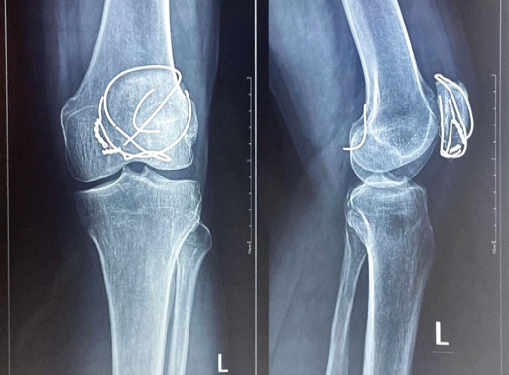

“Intra-Articular Intrusion of Broken Patella Cerclage Wire and the Importance of Higher Imaging in Its Rescue” – A Case Report

Adithyaa Sivaramakrishnan , Sitsabesan.C , P Gopinath Menon